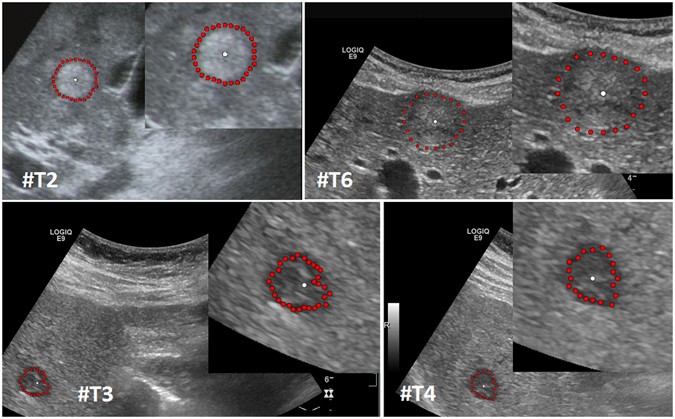

Figure 8

Segmentation results for different liver metastases (red dots). Presented are a hyperechoic metastasis of a neuroendocrine neoplasm of the pancreas (upper left), an isoechoic metastasis of a colon cancer (upper right) and two different views of a hypoechoic metastasis of an uveal melanoma (lower images). The white dots in the images are the user-defined seed points. At this positions the user stopped the interactive segmentation, because (s)her was satisfied with the automatic segmentation of the metastasis border. Note: figure adapted from26.